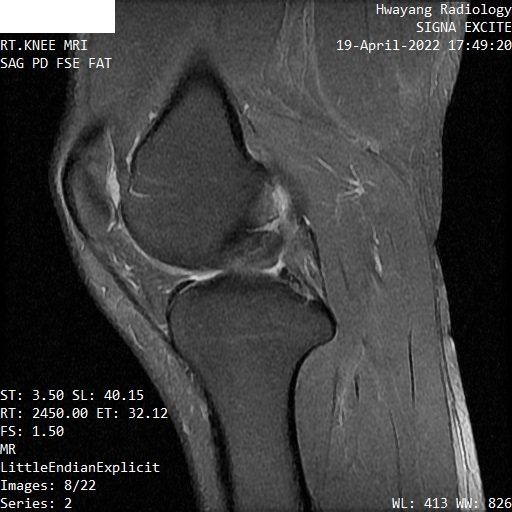

무릎연골 파열 mri좀 봐주세요 파열이 맞는지 궁금합니다.

오른쪽 무릎이 아파서 mri 찍어봤는데 집근처 병원에서 연골파열이라고 하는데

MRI 컷을 위와 같이 배열해놓은 것으로는 명확한 감별이 어렵습니다.

다만 연골부위의 MRI 상 이상 소견이 있는 것은 사실입니다.